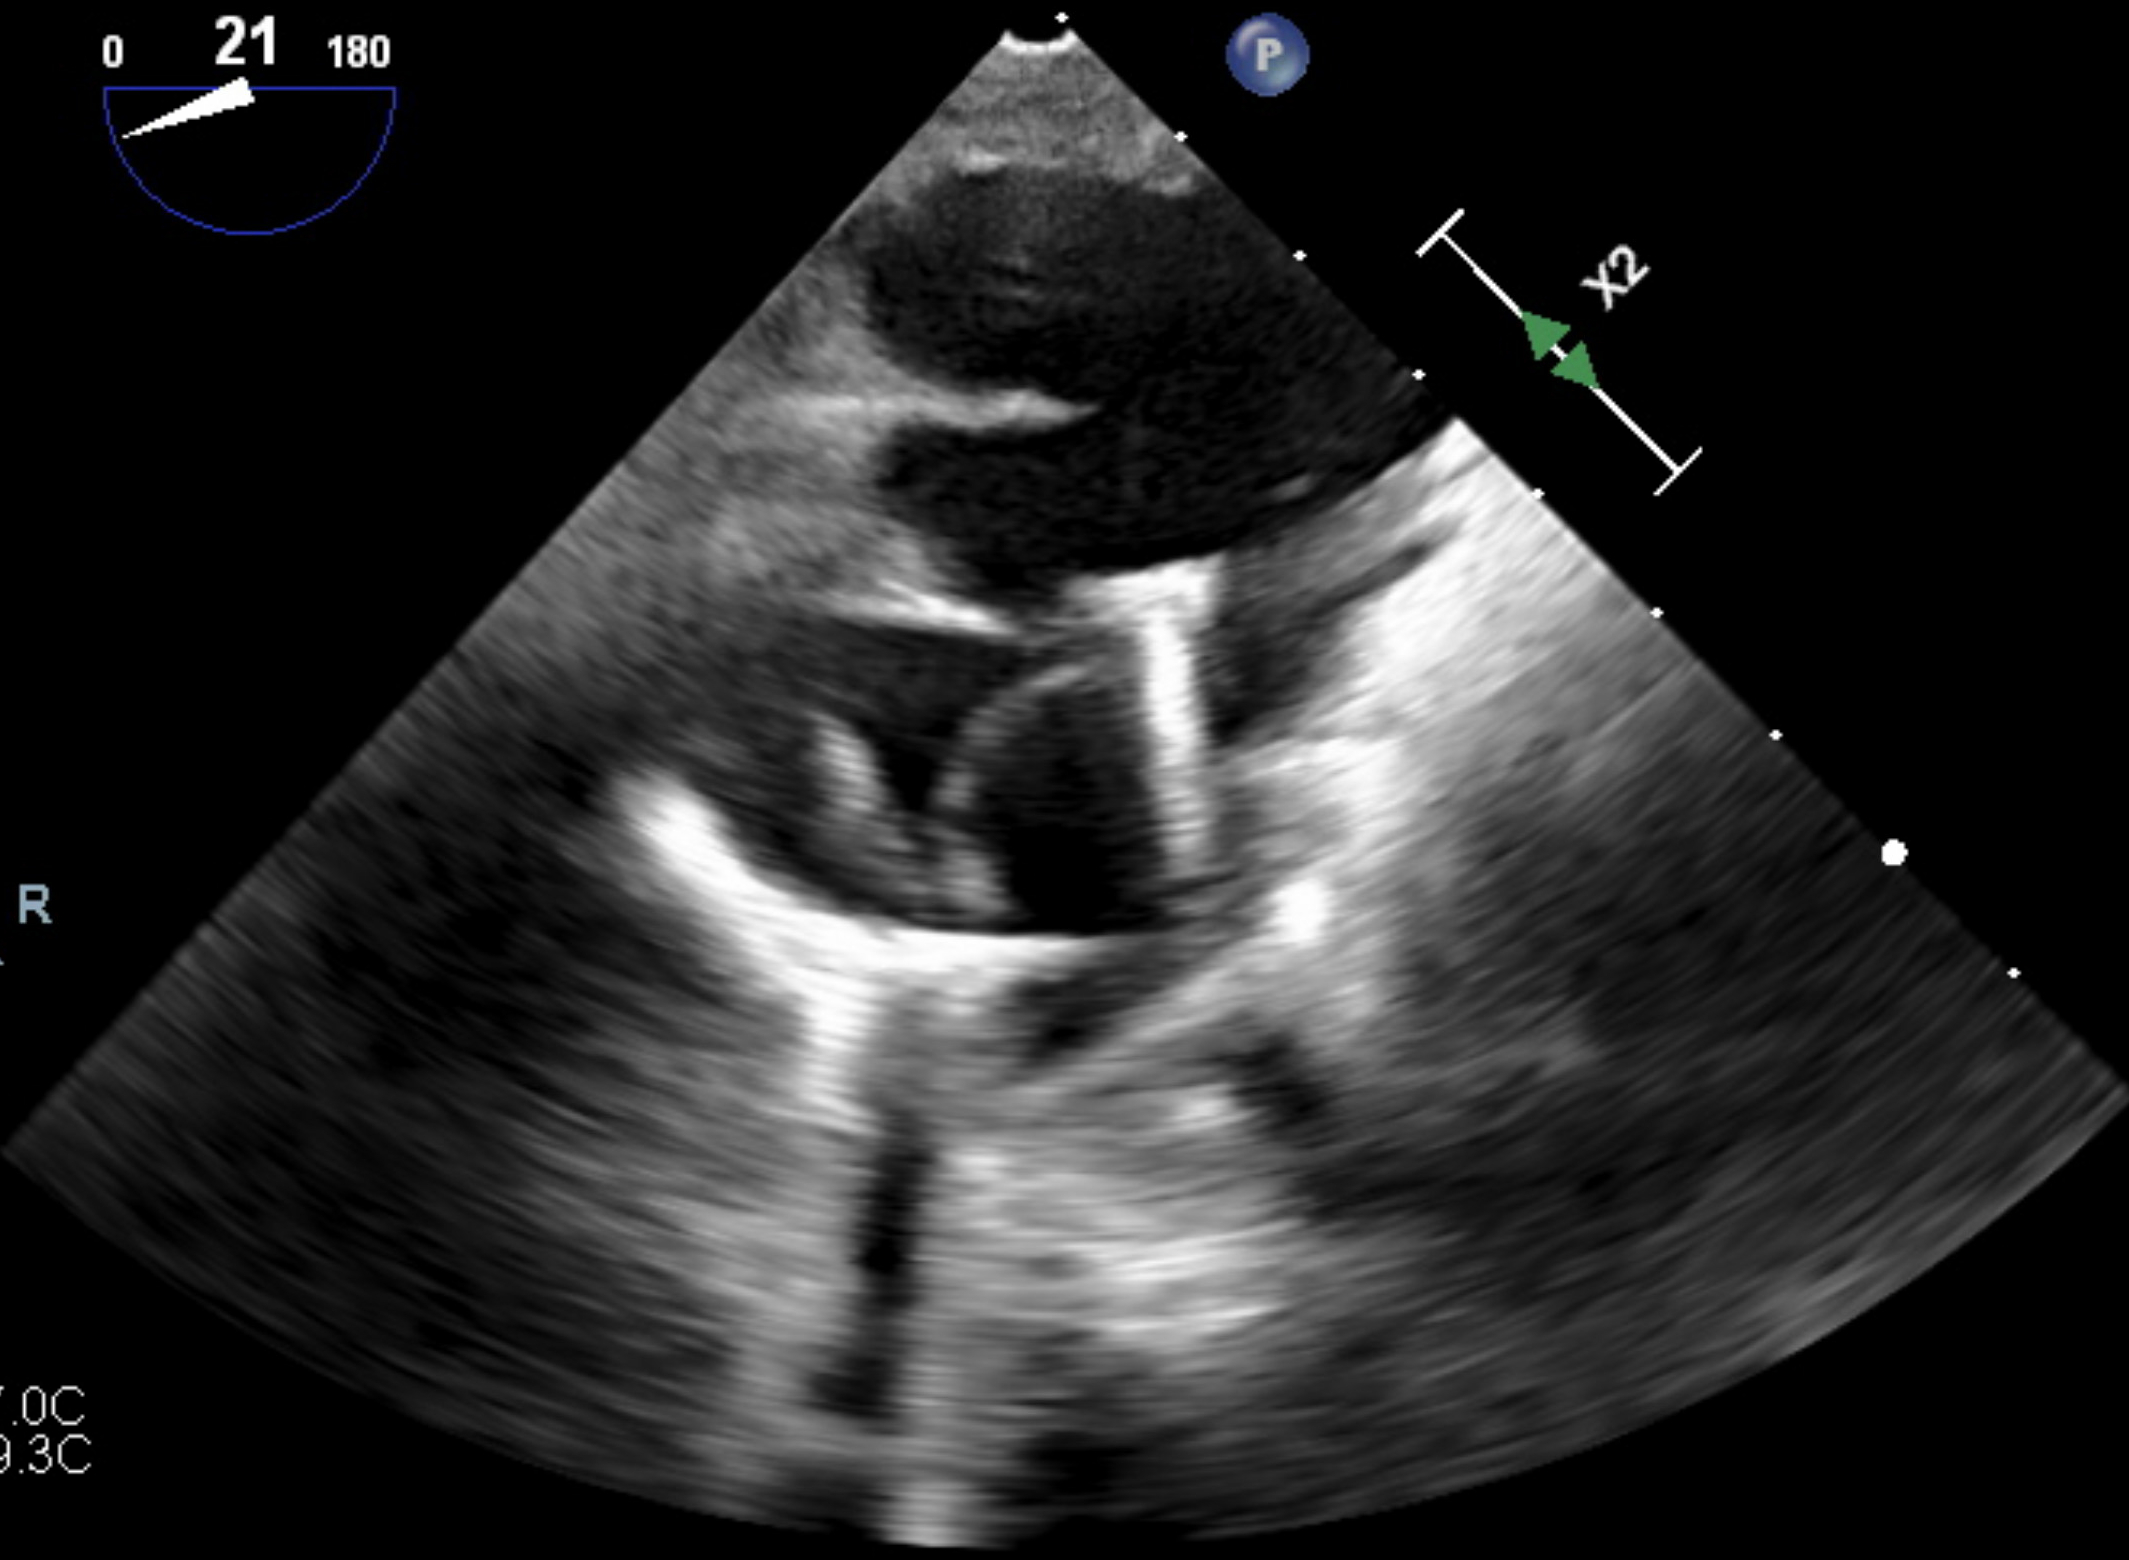

Case: A 53-year-old woman presented with acute dyspnea and orthopnea two months after a 33-mm Mitris Resilia tricuspid valve replacement for severe tricuspid regurgitation. Her history included mild aortic insufficiency and non-obstructive coronary artery disease. Transthoracic echocardiography revealed a large pericardial effusion with tamponade physiology, necessitating urgent pericardiocentesis. Transesophageal echocardiography demonstrated early SVD of the bioprosthetic valve, with poor leaflet coaptation, a central coaptation gap, and restricted anterior leaflet mobility. Extensive evaluation excluded infectious and autoimmune etiologies: blood cultures, inflammatory markers, viral serologies, thyroid function, and pericardial fluid cytology were unremarkable. Despite pericardial drainage, right atrial pressures remained elevated (mean 19 mmHg) on repeat right heart catheterization. Following a comprehensive heart team evaluation, a 29-mm Edwards Sapien valve was deployed via right internal jugular venous access within the failing surgical valve under fluoroscopic and echocardiographic guidance. Intraprocedural TEE demonstrated immediate reduction of tricuspid regurgitation severity to trace with a mean gradient of 1 mmHg. The patient had an uncomplicated recovery and was discharged the following day.